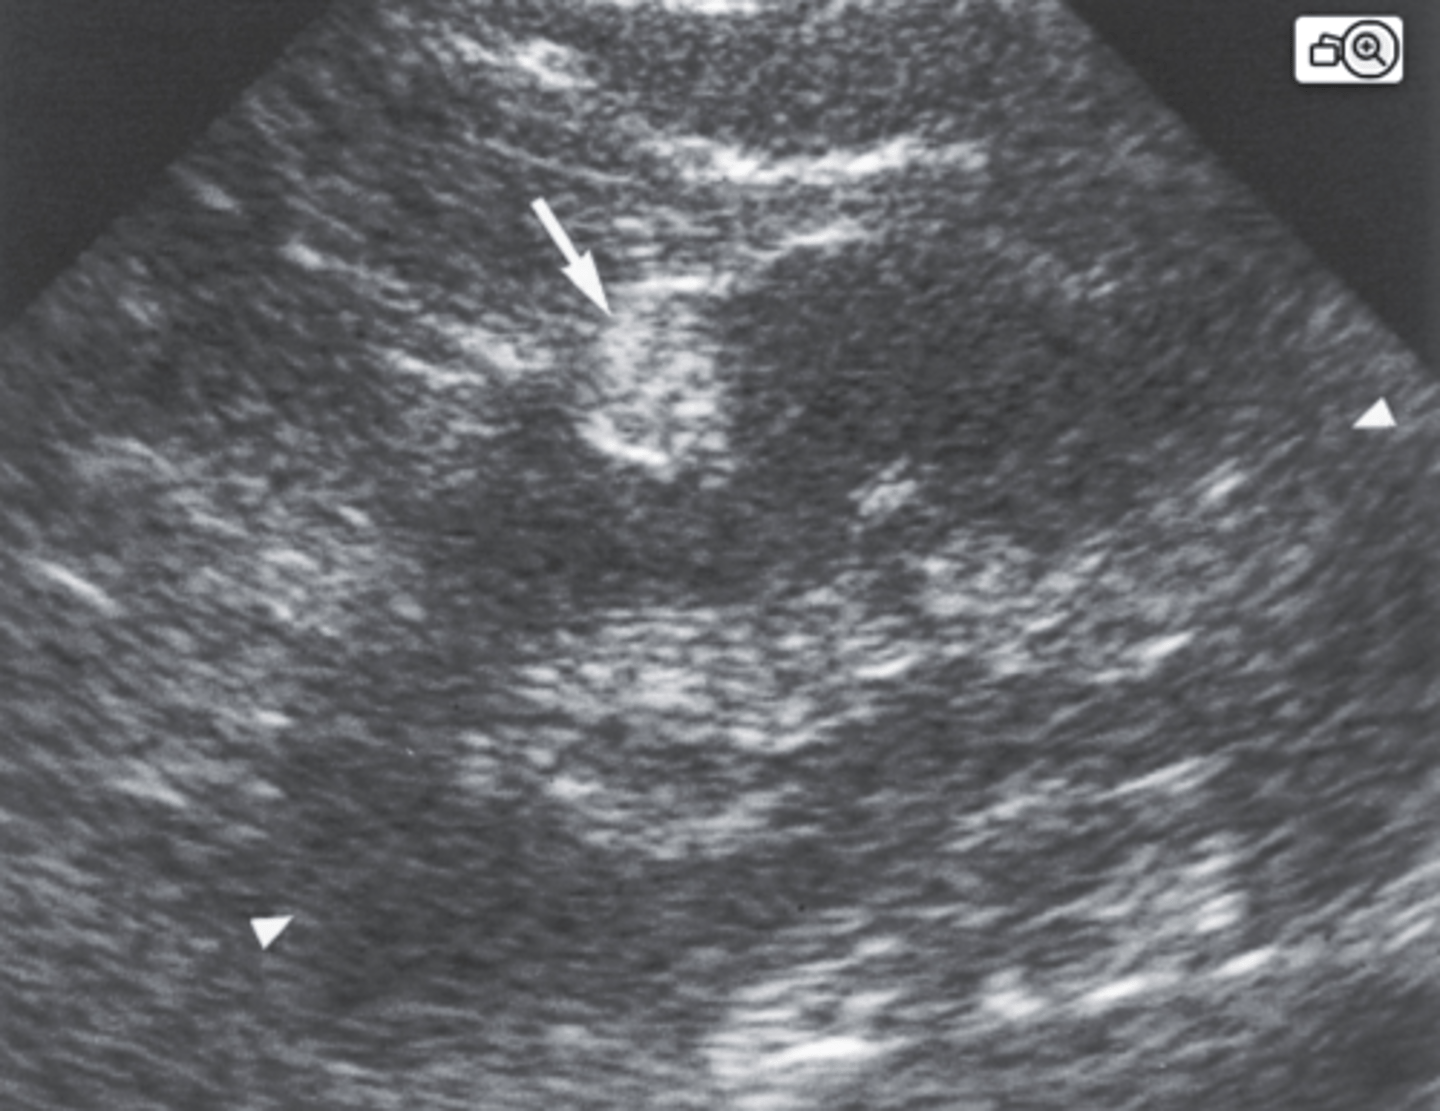

4. What is the arrow in Figure 7-41 most likely identifying in this asymptomatic patient?

a. Hypernephroma

b. Nephroblastoma

c. Renal hemangioma

d. Angiomyolipoma

11. What are the sonographic findings in Figure 7-44 consistent with?

a. Multiple renal hemangiomas

b. Medullary nephrocalcinosis

c. Renal lipomatosis

d. Schistosomiasis

12. Which of the following would be least likely associated with Figure 7-44?

a. Pyonephritis

b. Hypercalcemia

c. Urinary tract infection

d. Hyperparathyroidism